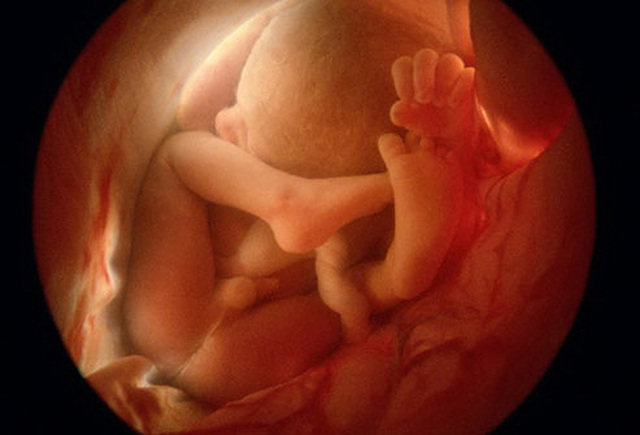

• Semana 28

Semana 28

28ª semana (7º mes): el feto pesa entre 1000 gramos y 1300 gramos. Las arrugas de la piel comienzan a desaparecer porque se deposita tejido graso debajo de la dermis. El cabello es más largo que los pelos del resto del cuerpo. Los bordes de los párpados, que estaban unidos desde el tercer mes, se separan. Los pulmones comienzan a adquirir movimientos respiratorios. El sistema nervioso central puede regular la temperatura y los movimientos respiratorios.